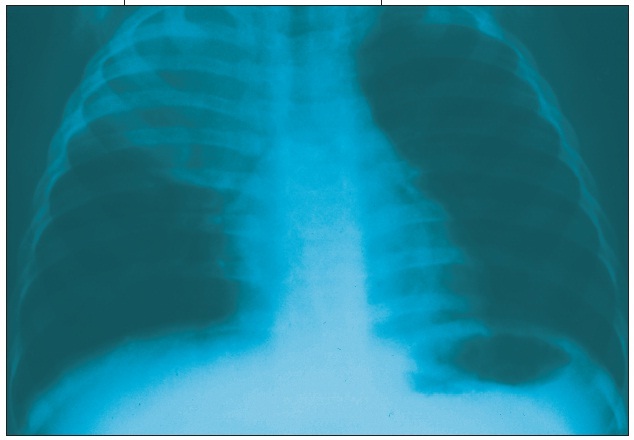

Linda S. Nield, MD; Deepak M. Kamat, MD, PhD; Prashant V. Mahajan, MD, MPH, MBA

<div id="article-content-body"> <p><img alt="Pneumonia" src="/sites/default/files/transfer/0509cfpPneumoniaIndex_thumb.jpg" style="height:62px; margin:5px;...